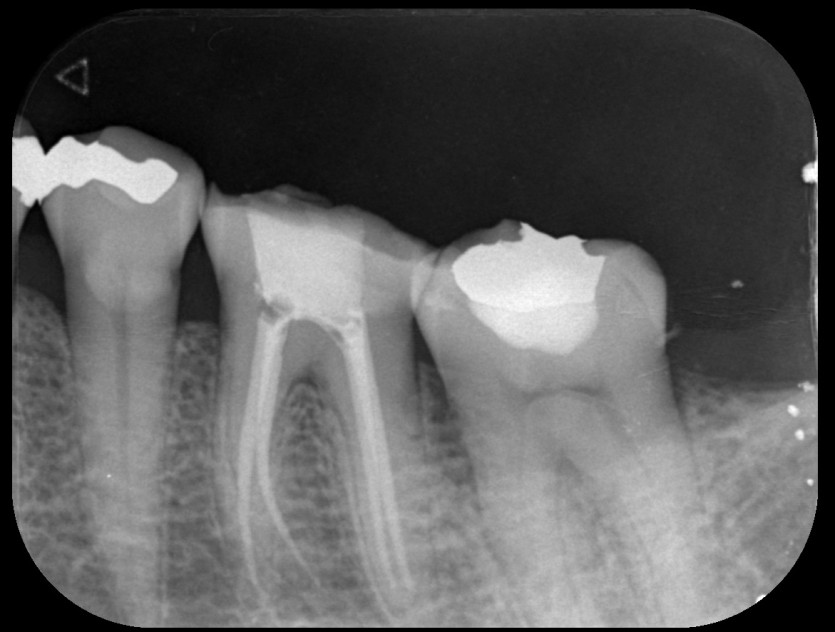

신경치료 사례